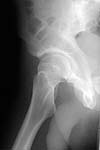

22 yrs man , semiprofessional( he earn some money from playing) basketball player got suffered in car accident.He had hip joint posterior luxation ( Pipkin 4) with little acetabular roof fragments ( nondisplaced) and anterosuperior abruption fracture of the head of the femur.

Additional injuries were severe face wounds. Emergency manipulations were reposition of the hip luxation under the radiologic control and wounds care. After reposition the CT scan was made. We found 2x3cm wide and 0.5 thick OCH fragment outside the joint surfaces , under the caput. The traction was applied.

i'd like to see post reduction x-rays to assess congruency of the reduction including AP & both Judet views. If the fragment is truly small, and extra-articular and the joint is stable, probably nothing needs to be done with the fragment, but i'd like more views! thanks

Here are the missing postreduction views.